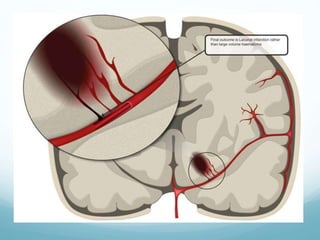

? An endovascular approach

to ICH